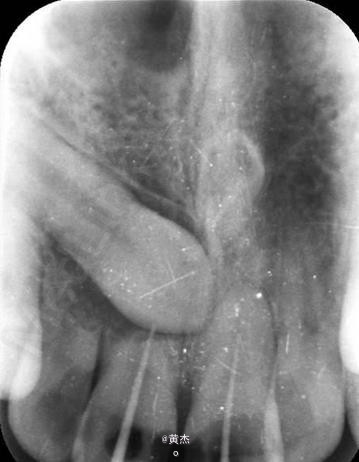

在11、21根管内放置牙胶尖后做x光检查:11、21牙根吸收至根中2/3.。 21未吸收,但测不到长度。正畸科通过CBCT检查,建议拔除13.。姑息保留11、12及手术探查21的根尖情况。

诊断:11、21根尖周炎。处理:11、21开髓无活力,大量血性渗出,根管无法测量。于是转诊口腔外科。术前和患者签知情同意书。给患者讲明外科手术有可能失败,最终拔除11、12、21的可能性。口腔外科处理:拔除13.。发现 11牙根几乎完全吸收、21唇侧牙根也被13牙冠压迫吸收到根中1/3。于是术中行11、21MTA根尖区封闭。12暂不做处理,观察半年后考虑进一步治疗方案。